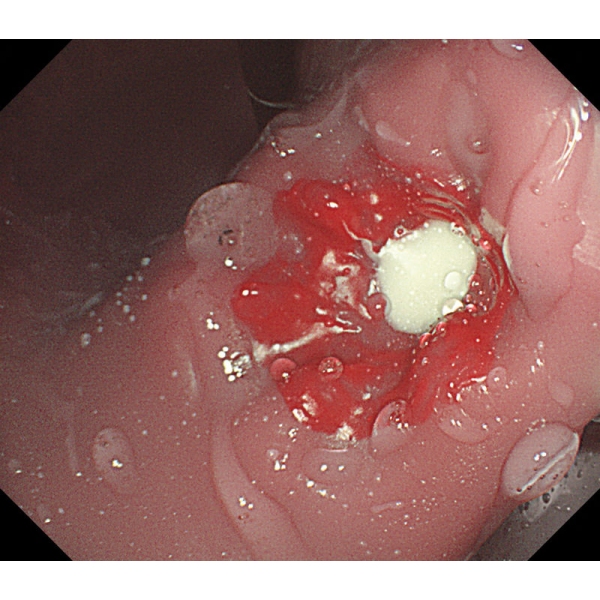

- V želodcu je mogoče opazovati želodčno razjedo in zgodnji rak želodca. Za opazovanje je mogoče pritrditi tudi štiri vrste polipov po Yamadovi klasifikaciji tipov od I do IV.

- V dvanajstniku je mogoče reproducirati razjedo.